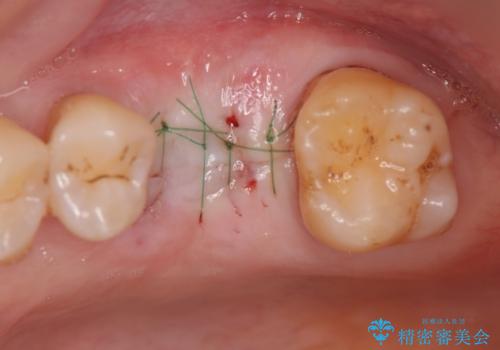

- 歯が割れてしまい、抜歯後のインプラント治療を希望され相談来院されました。

歯の喪失後に失われた咬合機能を回復するため、ブリッジ・入れ歯・インプラントの治療提案を行いました。

それぞれの長短所を検討し、隣接する歯を削らずにすみ、咬合機能をもっともしっかり回復できるインプラント治療を希望されました。

歯が割れるほどの咬合力が強い方でしたので、3本の歯を2本で支えるブリッジではなく、咬合負担能力の増えるインプラント治療にメリットが大きいと言えます。